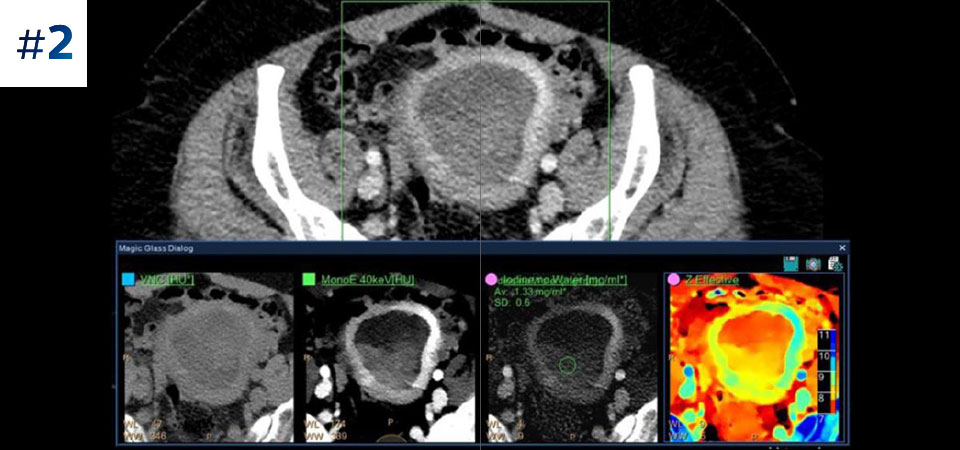

See the difference between spectral-detector CT and conventional CT

Learn about the advantages of spectral-detector CT